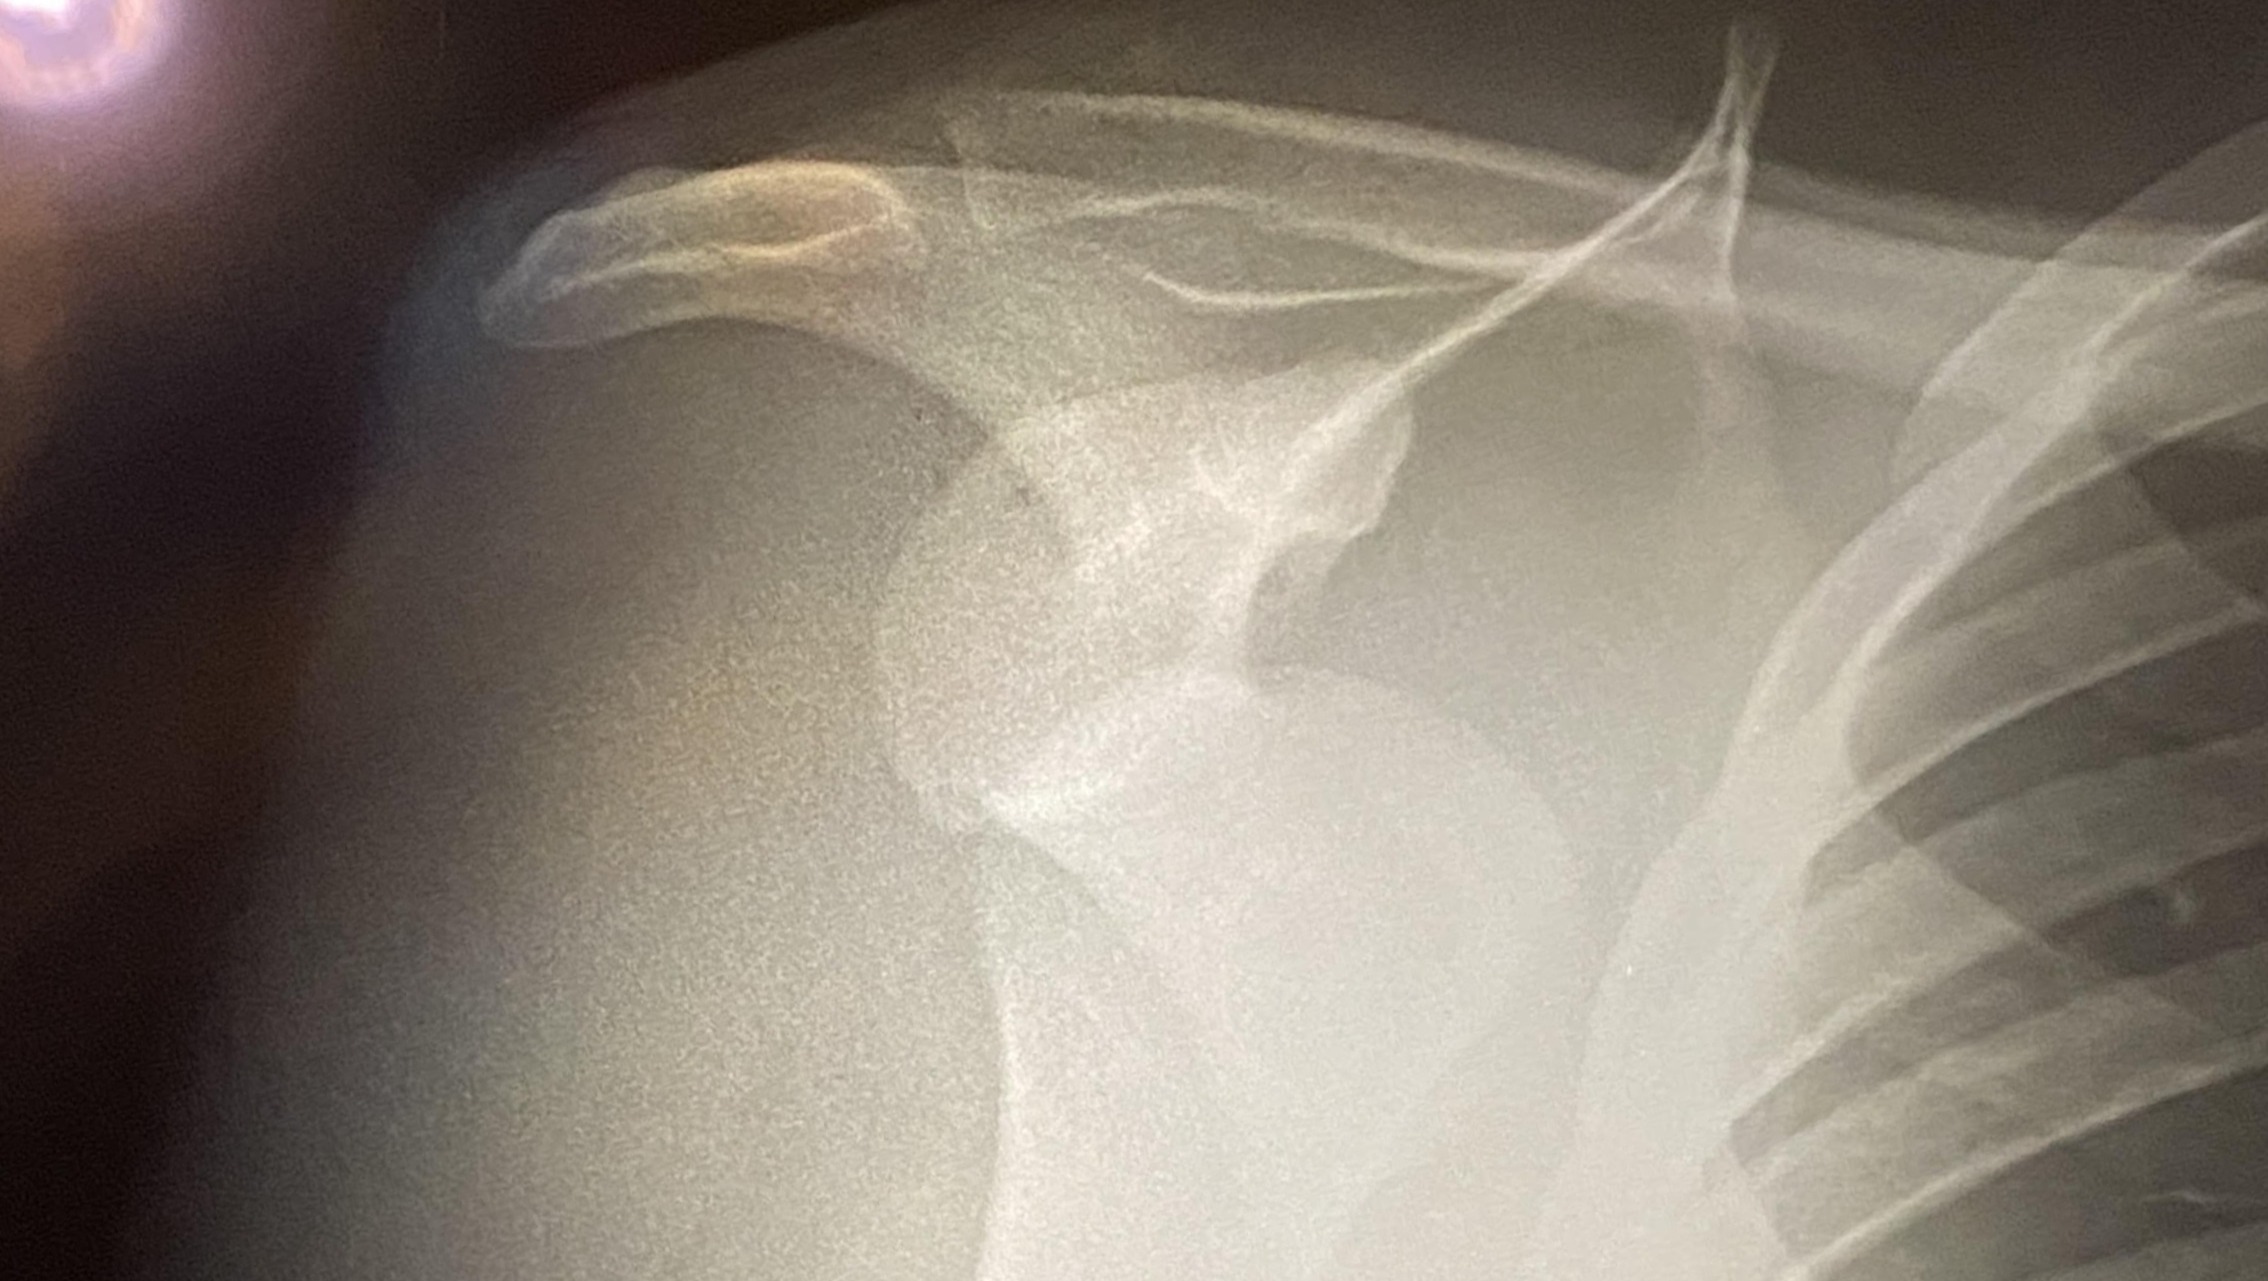

Recently, while surfing at Playa Zicatela in Puerto Escondido, I had a serious accident and dislocated my shoulder. What started as a normal day doing something I love turned into a painful injury that now requires ongoing medical care, physical therapy, and recovery time away from work and everyday life.

Unfortunately, the costs are quickly adding up—ER visit, imaging, consultations, and therapy sessions—and I do not have insurance. That’s why I’m asking for any help you might be able to offer.

Hace poco, mientras surfeaba en Playa Zicatela, Puerto Escondido, sufrí un accidente serio que resultó en una dislocación de hombro. Lo que comenzó como un día normal haciendo lo que más me apasiona, terminó en una lesión dolorosa que ahora requiere atención médica continua, fisioterapia y un proceso de recuperación lejos del trabajo y las actividades diarias.

Lamentablemente, los gastos médicos están aumentando rápidamente—visita al hospital, radiografías, consultas, y terapias—y no tengo seguro. Por eso recurro a ustedes, buscando un poco de ayuda.